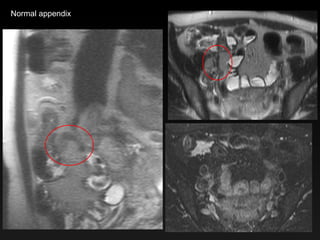

Normal appendix